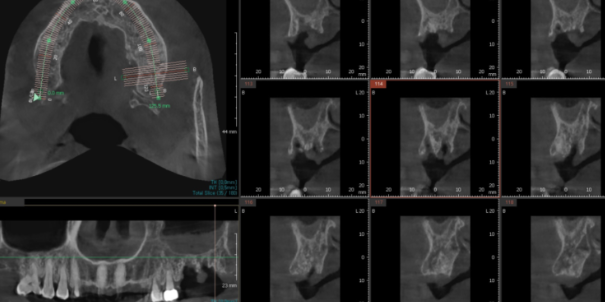

임플란트는 뼈에 심기 때문에

뼈 상태를 확인하기 위해 3d ct를 촬영하였습니다.

내비게이션 임플란트 기술로 분석을 시행

오차 없이 진행할 수 있었습니다.

231030

강일역 임플란트 치료 후 사진입니다.

치아 크라운 빠짐 부분과

잇몸이 내려갔던 치아

문제의 2개 치아를 발치 후

임플란트 완료하였습니다.